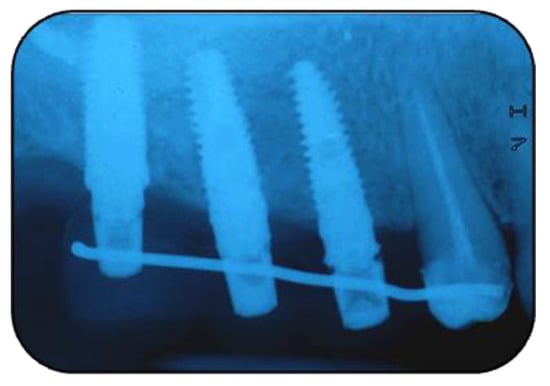

2.1. Surgical Procedures